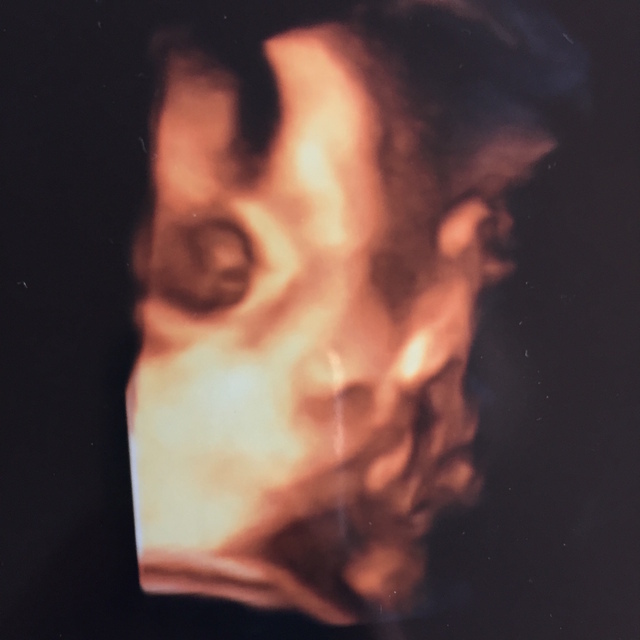

36週3日(36w3d・男の子)|Calie さん(30歳)

エコー写真撮影時のエピソード:

この写真をbaby dadに見せた時に、彼は大爆笑して「Why he looks so mad!? LOL」と一言。どうやら怒っているように見えると。(笑)

そう言われると、怒っているようにも見えてきて私も笑ってしまいました!